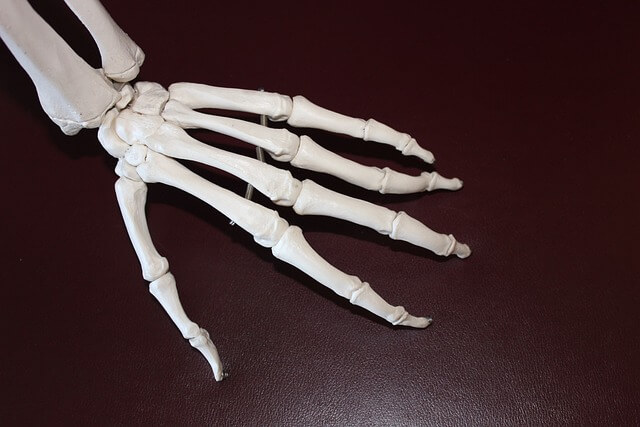

손가락 관절염은 많은 사람들에게 고통을 가져다주는 흔한 질병이고, 손과 손가락을 자주 사용하는 현대인들에게 특히 발생 빈도가 높은데요.

아래글에서는 손가락 관절염이 어떤 문제를 일으키고, 이를 관리하고 치료하는 방법에 대해 알아보겠습니다.

손가락 관절염에 좋은 운동

손가락 관절염에 좋은 운동은 손가락의 유연성을 유지하고 통증을 완화하는 데 도움이 됩니다. 아래는 손가락 관절염에 효과적인 몇 가지 운동법을 소개합니다.